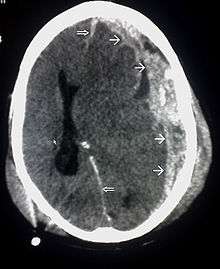

| CT scan showing cerebral contusions, hemorrhage within the hemispheres, subdural hematoma, and skull fractures[1] | |

One type of focal injury, cerebral laceration, occurs when the tissue is cut or torn.[30] Such tearing is common in orbitofrontal cortex in particular, because of bony protrusions on the interior skull ridge above the eyes.[24] In a similar injury, cerebral contusion (bruising of brain tissue), blood is mixed among tissue.[15] In contrast, intracranial hemorrhage involves bleeding that is not mixed with tissue.[30]

Hematomas, also focal lesions, are collections of blood in or around the brain that can result from hemorrhage.[3] Intracerebral hemorrhage, with bleeding in the brain tissue itself, is an intra-axial lesion. Extra-axial lesions include epidural hematoma, subdural hematoma, subarachnoid hemorrhage, and intraventricular hemorrhage.[31] Epidural hematoma involves bleeding into the area between the skull and the dura mater, the outermost of the three membranes surrounding the brain.[3] In subdural hematoma, bleeding occurs between the dura and the arachnoid mater.[15] Subarachnoid hemorrhage involves bleeding into the space between the arachnoid membrane and the pia mater.[15] Intraventricular hemorrhage occurs when there is bleeding in the ventricles.[31]